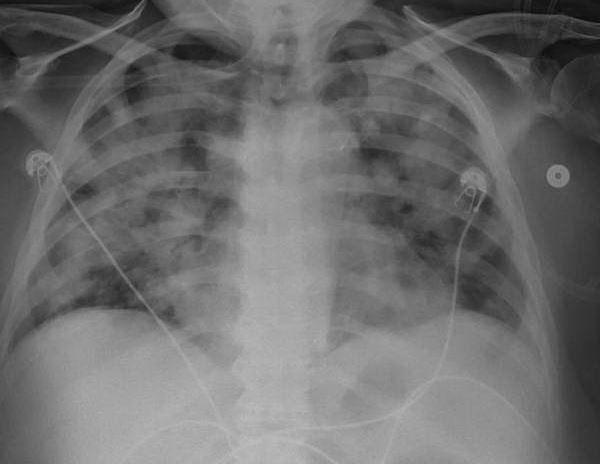

A 68 year old female patient with history of diabetes mellitus type 2, chronic kidney disease III (baseline serum creatinine of 2 mg/dl) and recently diagnosed pulmonary hypertension after a right heart catheterization presented to the emergency room with odynophagia, hoarseness and dyspnea of a week duration. She had a flexible nasopharyngolaryngoscopy (NPL) which showed an ulcer at the base of the tongue and marked laryngeal edema. She was also found to have an elevated serum creatinine level at 3.12 mg/dl. She was admitted to the intensive care unit for airway monitoring. She had a biopsy of the tongue ulcer which showed nonspecific inflammation without atypia. She received Dexamethasone for her laryngeal edema. She initially improved however 2 days later she experienced acute hypoxic respiratory failure requiring noninvasive positive pressure ventilation and later mechanical ventilation. Chest X-ray and CT thorax were consistent with pulmonary edema. She was also noted to have anuria at that time with a rising serum creatinine level at 4.44 mg/dl. She had pinkish bloody tracheal aspirate which raised concerns for diffuse alveolar hemorrhage, as a result an autoimmune workup was done. This was positive for ANA, anti dsDNA antibodies and hypocomplementemia (low C3,C4). She was started on continuous veno-venous hemofiltration and underwent a renal biopsy. Pathology was positive for background diabetic glomerulosclerosis by light microscopy, weak full house pattern by immunofluorescence corresponding to occasional subendothelial and rare mesangial deposits by electron microscopy. This was felt to be representative of class III lupus nephritis. She was continued on Dexamethasone and Mycophenolate Mofetil was added to her immunosuppressive regimen. She had improvement in her urinary output and respiratory status thereafter and was able to be successfully liberated from the ventilator and dialysis was discontinued. She had repeat NPL a week after which showed improvement in laryngeal edema. She was eventually able to be discharged on Prednisone and Mycophenolate and was seen in the rheumatology clinic multiple times after.